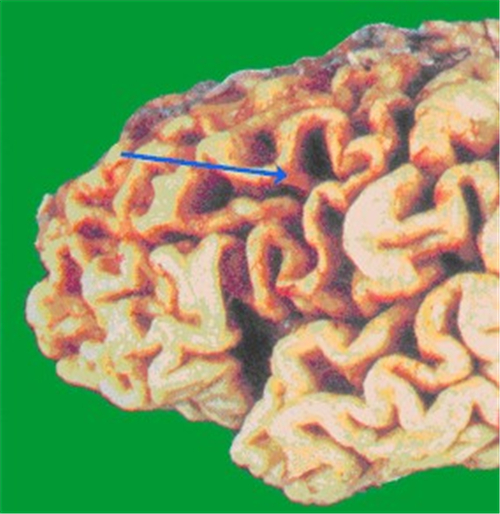

橄欖橋腦小腦腦萎縮標本